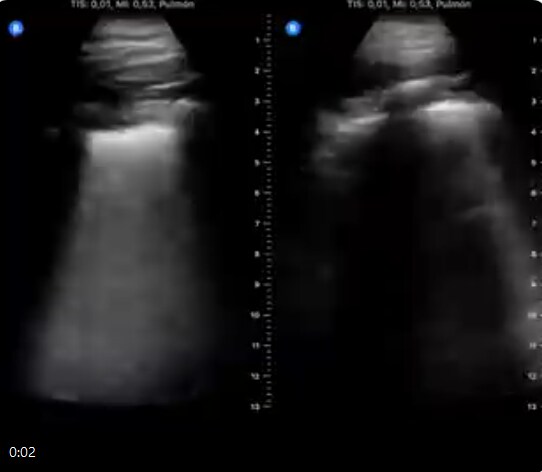

35 वर्षीय येल तुंग चेन डॉक्टर अपने घर में आइसोलेशन (एकांत) में रह रहे हैं. इस दौरान वे अपने फेफड़ों और शरीर में होने वाले परिवर्तन और दर्द की डायरी को लाइव-ट्वीट कर रहे हैं.

उन्होने ट्वीट में लिखा है कि पहले दिन उन्हें गले में खराश और सिरदर्द रहा लेकिन फेफड़ों में समानता नहीं थी. वहीं चौथे दिन चेन ने कहा कि उनका गला और सिर दर्द ठीक हो गया है. उनकी खांसी में सुधार हुआ, हालांकि उन्हें दस्त थे. उनके फेफड़ों में तरल पदार्थ अभी भी मौजूद था. बताया जा रहा है कि उनका इलाज जारी है. उनकी हालत में पहले से सुधार है.